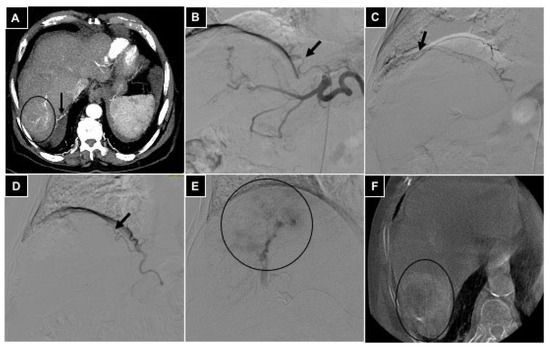

| 2 TAE | Gastric cancer | 2 Left hepatic a. | Left gastric a. | Bland microparticles |